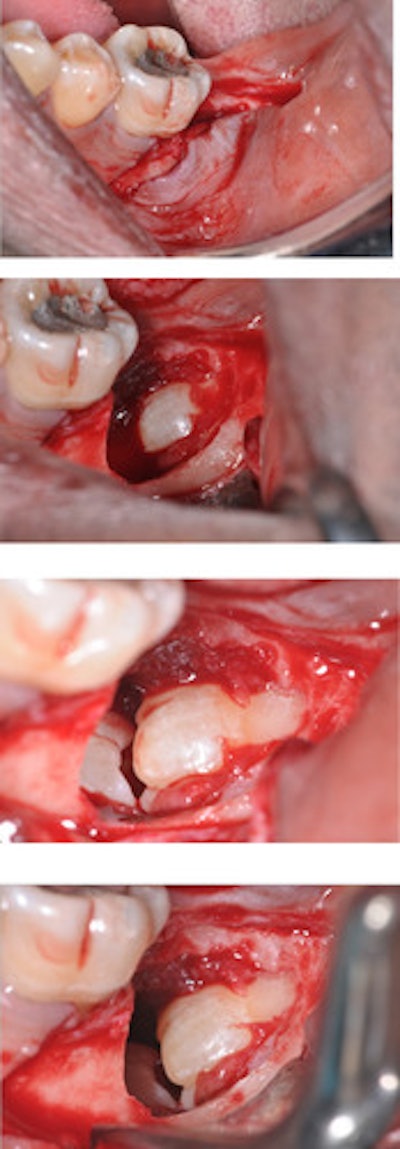

The man underwent a biopsy of the lesion in the lower left quadrant, and lab tests confirmed it was a dentigerous cyst. After discussions with an oral and maxillofacial consultant, the patient agreed to have the upper right teeth #7 and #8 and the lower kissing molars extracted due to the risk of damage to the inferior alveolar nerves. The man underwent the procedure and was given analgesics and a chlorhexidine rinse and had a successful recovery, according to the report.

At a three-month visit, the soft tissue had healed completely, and the patient reported no other symptoms, the authors wrote.